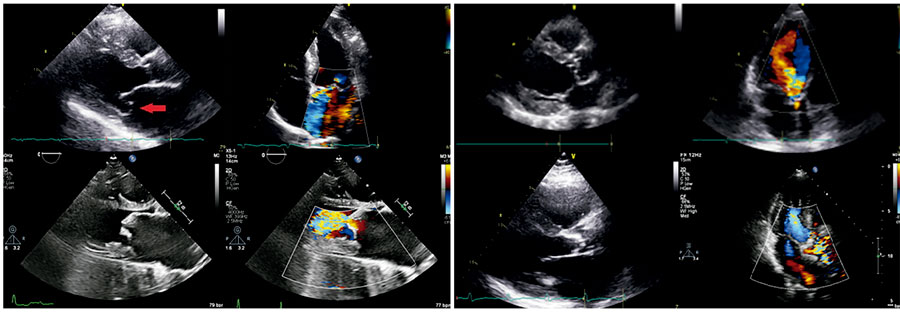

Valvular heart disease is increasingly prevalent, and bedside confirmation or exclusion of severe disease is needed to enable a rapid and cost-effective diagnostic workup. The physical examination skills of clinicians are insufficient for accurate diagnosis, making complementary tests generally necessary. Despite being commonly requested, electrocardiography and chest radiography present low positive and negative likelihood ratios. Incipient studies involving artificial intelligence have shown promising opportunities to support the diagnosis. In addition, solid current evidence demonstrates that point-of-care ultrasound enhances bedside diagnosis of several cardiovascular conditions. Echocardiographic skills can be acquired after only a few hours of training, which encourages routine bedside use with handling equipment. Despite the routine use of sonography in emergencies, large-scale simplified screening protocols for valvular disease remain lacking. Therefore, improving the accuracy of valvular heart disease diagnosis by integrating all bedside modalities needs to be better understood. We propose a simple, reproducible five-step point-of-care ultrasound protocol for diagnosing valvular heart disease (the ValvUS approach), applicable to all patients. The proposed visual assessment involves evaluating valvular movement, thickness, regurgitant flow, aliasing, and chamber dimensions. This evaluation should be interpreted in the context of traditional clinical probability to ensure the most accurate bedside diagnosis. Typical findings of severe valvular disease on electrocardiography and chest radiography, and particularly on point-of-care ultrasound, may improve the accuracy of bedside diagnosis after clinical assessment in the near future.